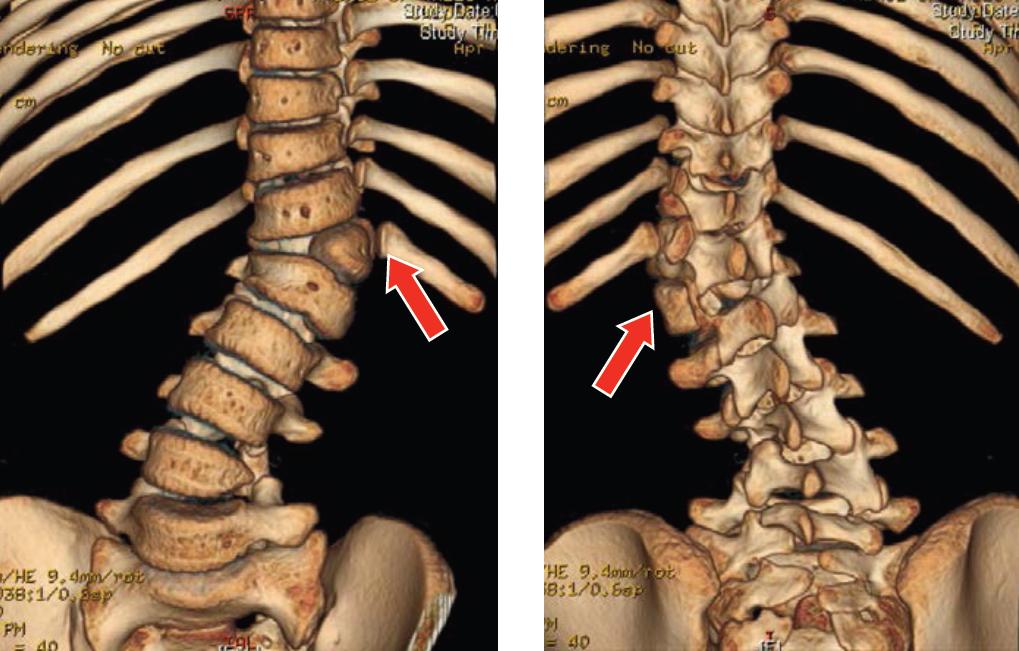

Congenital scoliosis

![]() Fig. 3 3D-CT scan of patient with left T12 hemi-vertebra. |